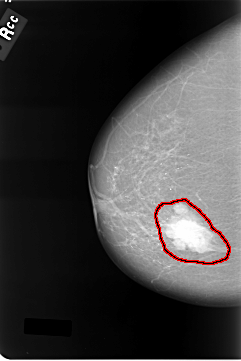

C_0011_1.RIGHT_MLO

FILE: C_0011_1.RIGHT_MLO.OVERLAY

TOTAL_ABNORMALITIES 1

ABNORMALITY 1

LESION_TYPE MASS SHAPE LOBULATED MARGINS CIRCUMSCRIBED

ASSESSMENT 5

SUBTLETY 5

PATHOLOGY MALIGNANT

TOTAL_OUTLINES 1

BOUNDARY